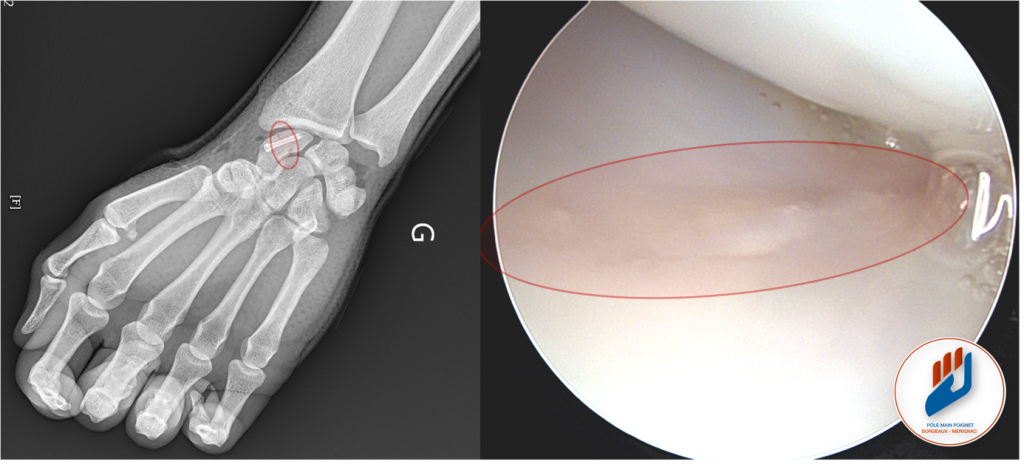

En revanche, si la fracture est déplacée, instable ou si elle tarde à consolider, une intervention chirurgicale est nécessaire. Cette chirurgie consiste à fixer l’os avec une vis (le plus souvent sous contrôle arthroscopique et, si besoin, d’y associé à une greffe osseuse.

Le traitement chirurgical de la fracture du scaphoïde se déroule sous anesthésie locorégionale, ce qui permet d’endormir uniquement le bras. Le plus souvent le traitement se fait par une courte incision. Si une arthroscopie est associée, deux petites incisions sont réalisées sur le dos du poignet pour introduire une caméra miniature et des instruments spécifiques.

La fracture est soigneusement reduite sous contrôle visuel direct. Si besoin, un greffon osseux spongieux est ensuite prélevé au niveau du radius distal, à proximité immédiate du site opératoire et positionné dans le foyer de fracture. La fracture est ensuite stabilisée à l’aide d’une vis ou de broches, selon le cas.

L’intervention est rapide, précise, et réalisée en chirurgie ambulatoire. Le patient peut rentrer chez lui le jour même, avec une immobilisation adaptée.